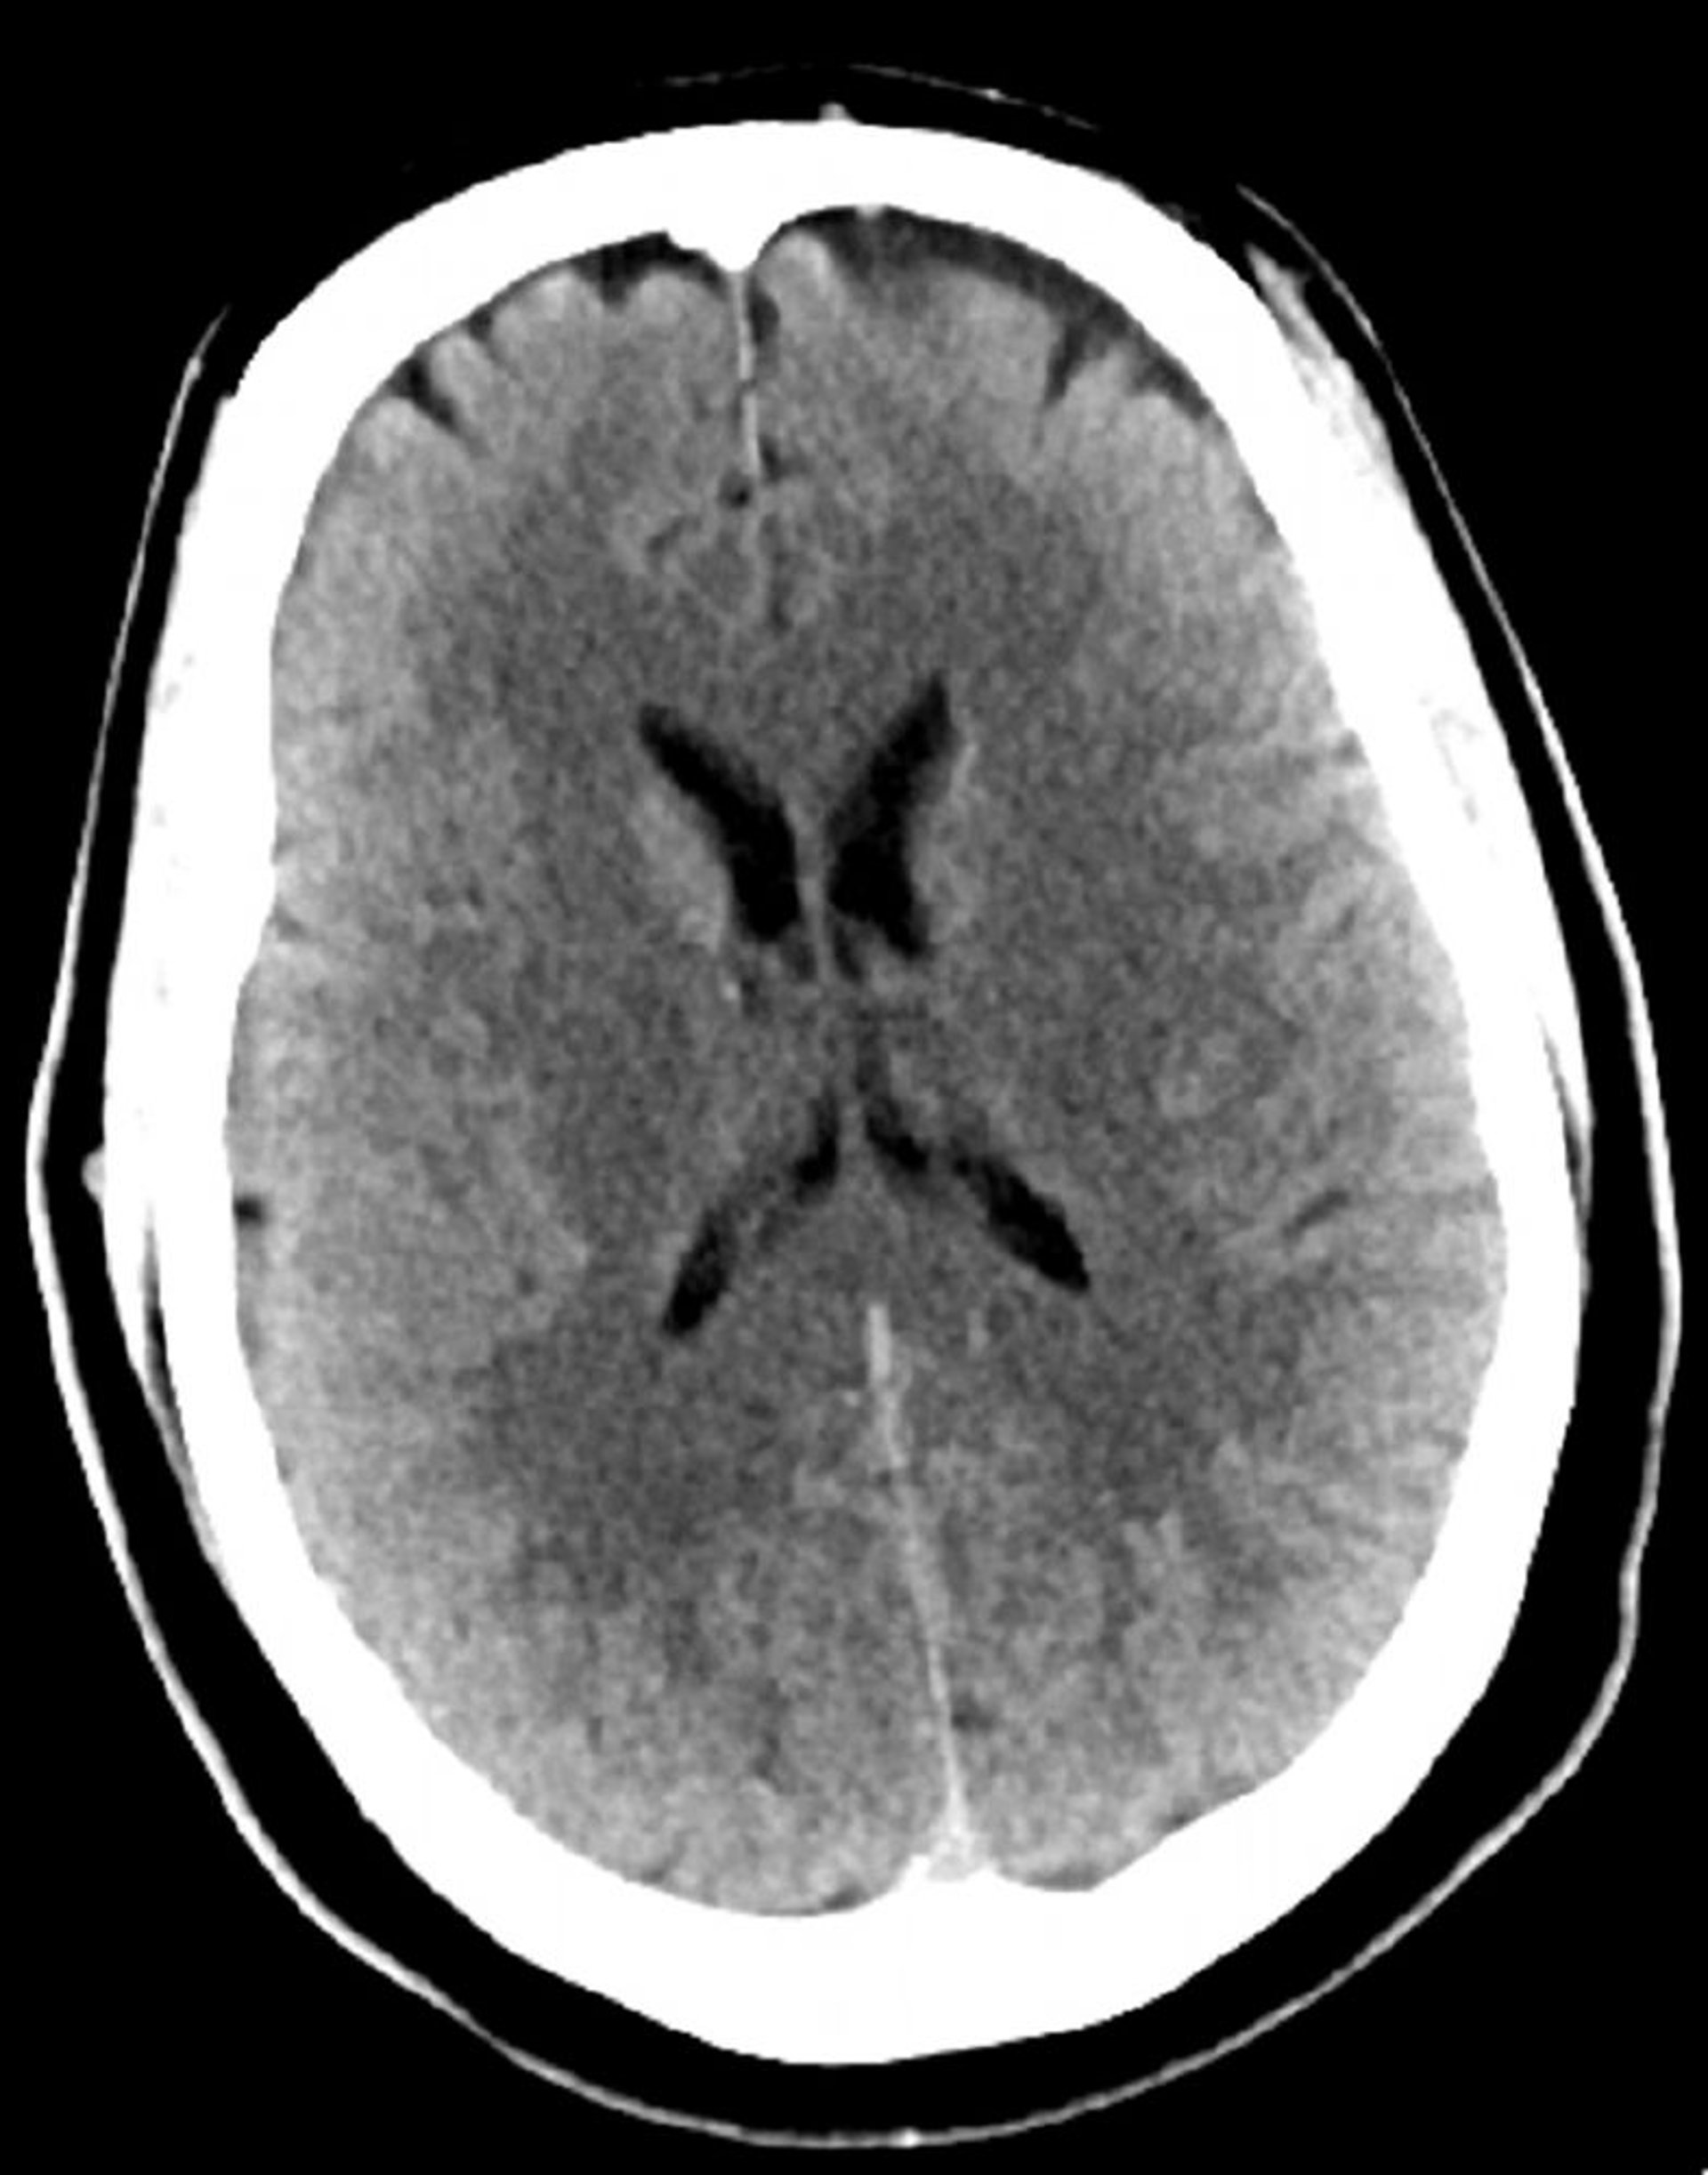

Tomografía computarizada craneal normal (adulto, 30 años)–diapositiva 4

Esta imagen es una tomografía computarizada craneal normal correspondiente a un adulto joven de 30 años de edad. No hay hemorragia o líquido intra- o extra axial. Se conserva la diferenciación gris-blanco. El tamaño ventricular y el patrón sulcal son normales.